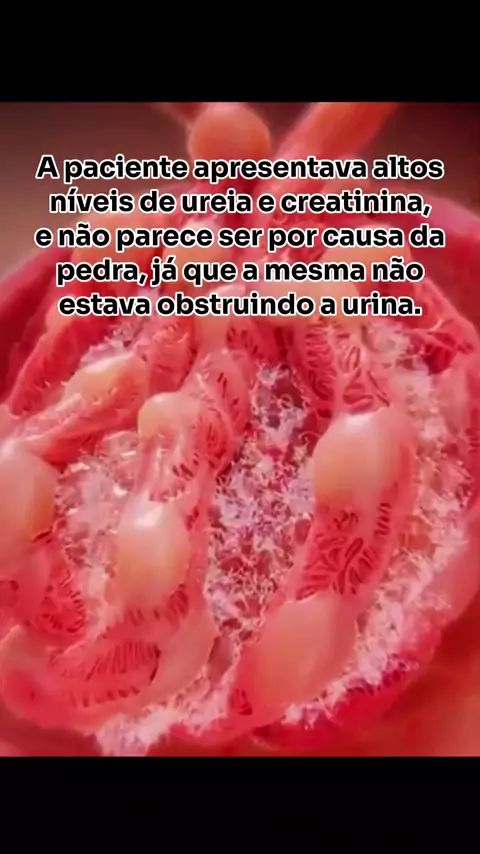

E aí? Qual a hipótese? #medicina #saude # #viral #explorar

E aí. O que pode ser? . . . #medicina #saude #mulher #explorar